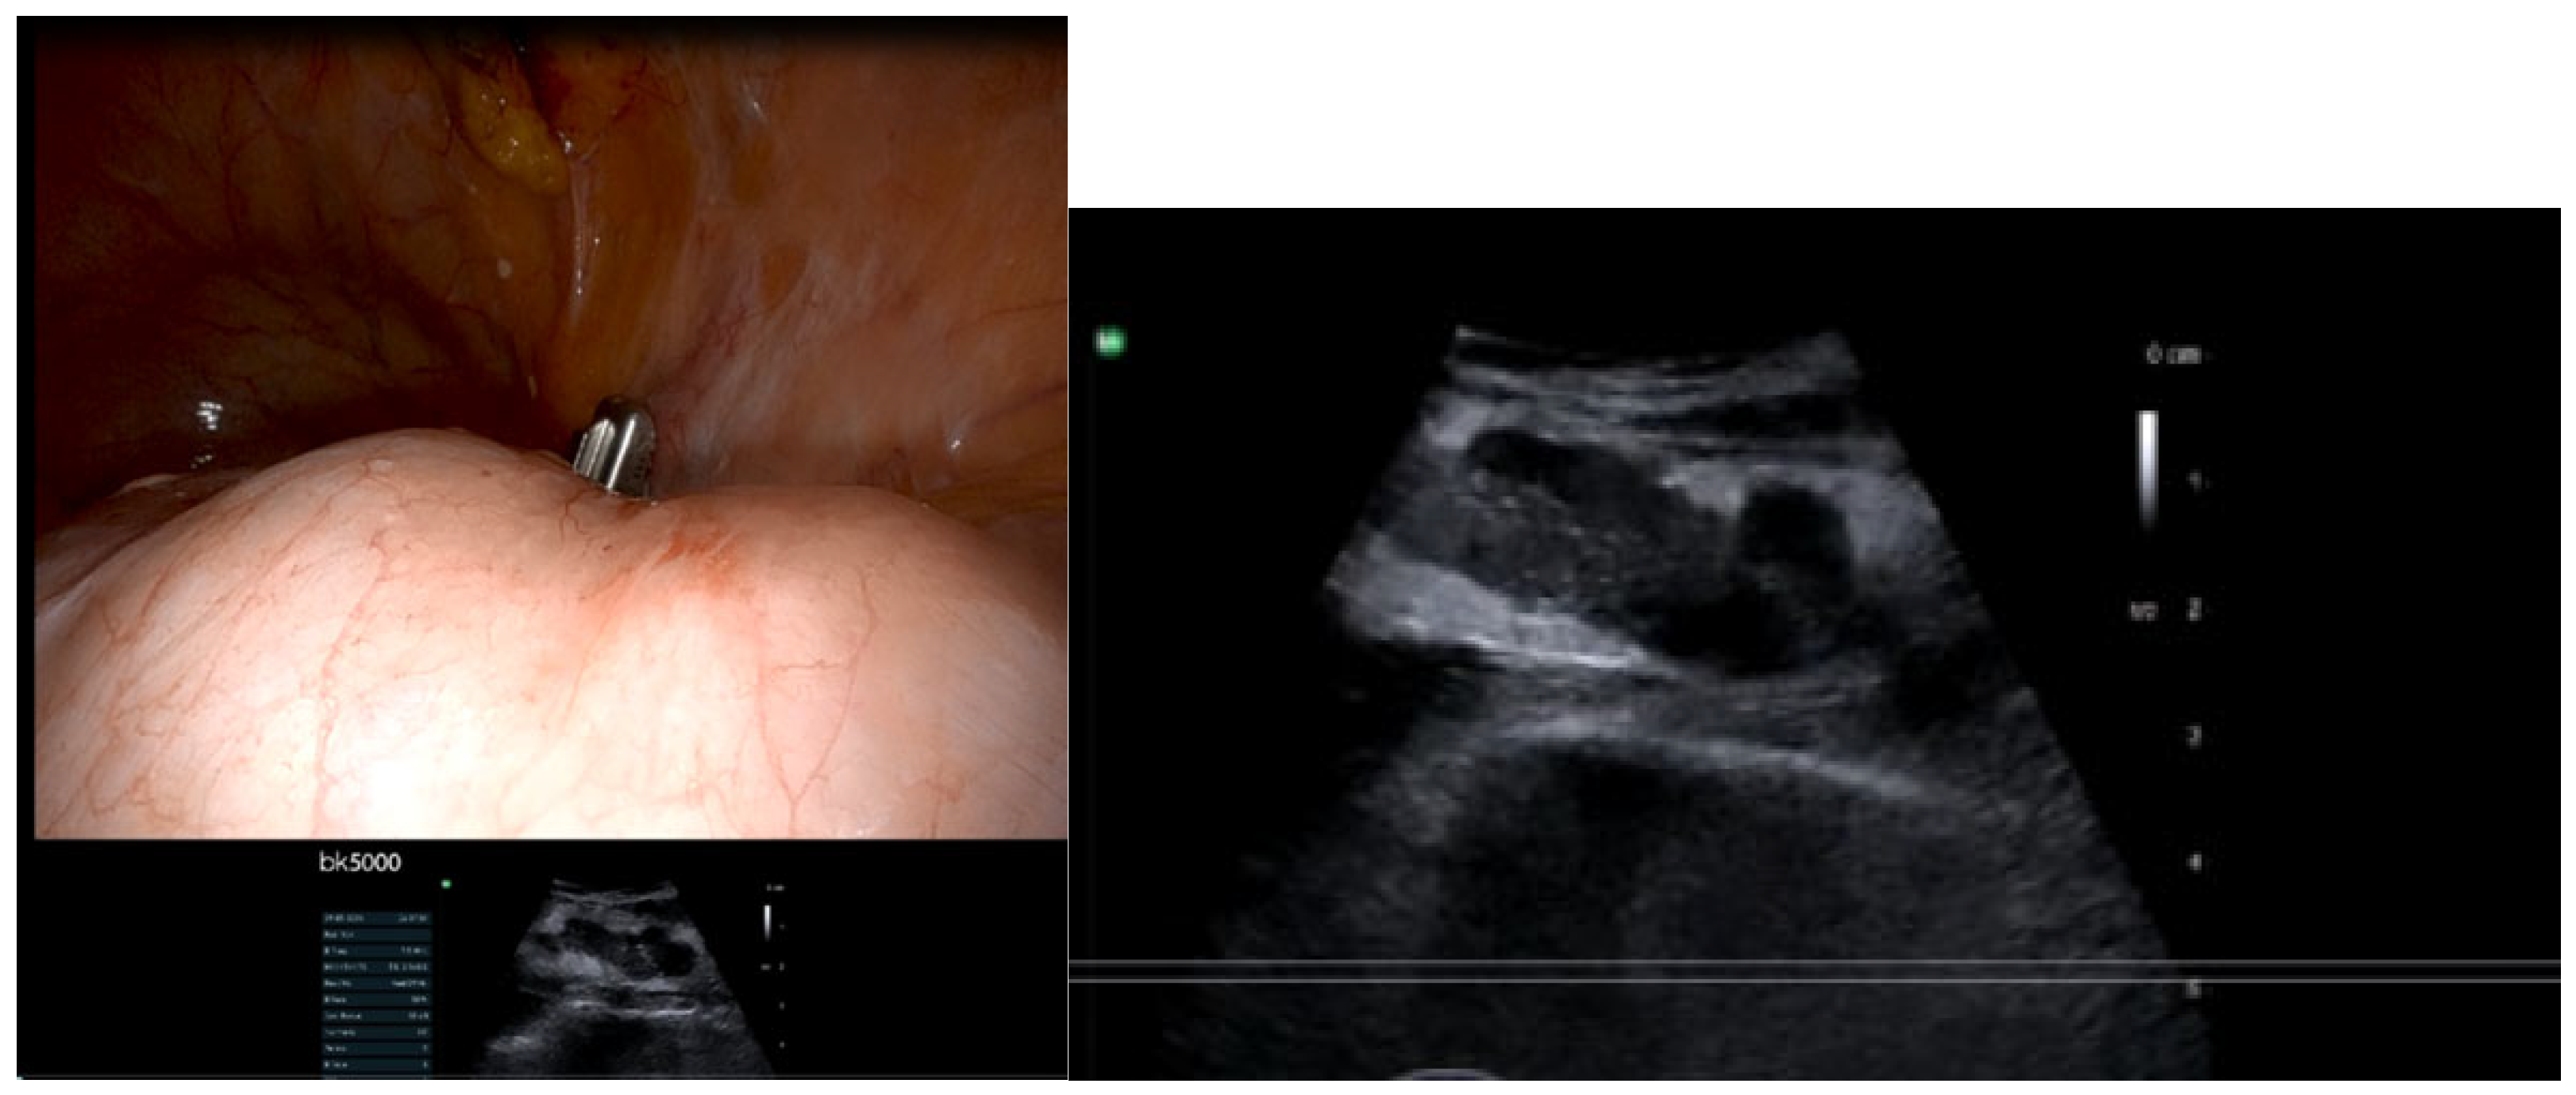

- IOUS in gynecological oncology lymph node assessment and staging

- Real-time confirmation of suspicious nodes before excision

- Immediate assessment of resection completeness

- Identification of critical vascular relationships to prevent injury